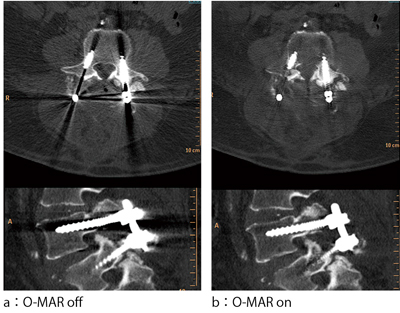

この再構成技術は,イメージ上から一定の閾値により,金属部分とそれ以外の組織分類を行い,forward projectionにより,金属のみのサイノグラムを作り出す。これをオリジナルサイノグラムとサブトラクションを行い,金属のないサイノグラムとアーチファクト部分のイメージを生成する。そして,補完が必要となる欠損した部分を同定し,iterative error correctionの繰り返しにより,補正する5)(図3)。その際,画像は,オリジナルとO-MARの2種類を作成するように設計されており,両者を比較観察して使用することを推奨している。このように,O-MARは,これまでのフィルタ処理とは異なり,周辺構造物のコントラストや分解能の劣化を制御しているため,通常の再構成と比べて,金属アーチファクトによるデータ欠落部の回復と周辺分解能の維持,期待する(120kV)画質を得られるという特長を持つ(図4)。

■O-MAR臨床応用

O-MARは,整形外科領域での金属インプラントを対象とした再構成技術であり,大きく期待される領域としては,人工股関節形成術や後方椎体間固定術などの術後フォローアップCTにおいて,周辺構造物である骨癒合などの評価や(図5),整形外科以外のオーダにおいても,金属アーチファクトのために目的部位の観察が困難な症例すべてに有効だと考える。ほかにもニーズの高い領域としては頸部CTA検査が挙げられ,口腔インプラントのアーチファクトによる血管の欠損を防ぐ効果が期待できる(図6)。

図5 後方椎体間固定術画像